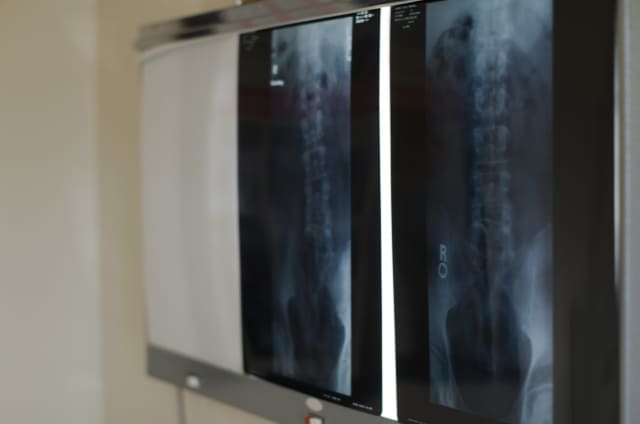

1.腰痛の検査を画像診断しか頼りにしない

腰痛で整形外科の外来に行くと、まず腰痛が起こった時期や痛みの程度、本人が自覚している原因、これまでかかった病歴などを聞かれます。これが問診です。そして、腰痛の原因を調べるといわれ、レントゲン撮影やMRIなどの画像診断が行われます。

医師は、検査画像をみながら「ここにヘルニアが起きています」「ここが狭窄を起こしています」と指摘し、「ここで神経が圧迫されている痛みが起こっています」と患者さんに説明します。

画像診断にて変形し、歪んだ腰椎をみた整形外科医が「神経が圧迫されていることが原因の腰痛」と反射的に診断します。なぜならそれ以外の腰痛の原因を知らないからです。

画像診断で異常があっても、その異常が見られるはずの神経の支配する筋肉の萎縮、筋力の低下、知覚神経の低下、反射の低下、消失これらを調べる神経学的検査を行い、その神経支配領域と合致する結果が出た際のみ、ヘルニアや狭窄症などの確定診断を受けることができます。

画像診断だけをみて、患者さんの身体を触れずに診断を下す整形外科医には、本当の原因はわかりません。

4.MRIなど画像診断の限界

これまでの整形外科では、腰痛の原因を主に脊椎の骨、関節の変形と椎間板の老化による変性に答えを求めてきました。それらの異常をレントゲン撮影やMRIなどの画像診断でとらえることで、原因を特定できていたと思っていました。

しかし、腰痛の大半は、画像診断などの検査では脊柱に異常が見られないのに、痛みが起こっています。

また、逆に画像では、椎間板が突出しているヘルニアや脊柱が変形しているなどの異常が確認できるが、腰痛などの症状が全く現れない場合もあります。例えば、健康診断で、胸部のレントゲン撮影後、変形が確認できるが、腰痛などの症状が全くないなど。